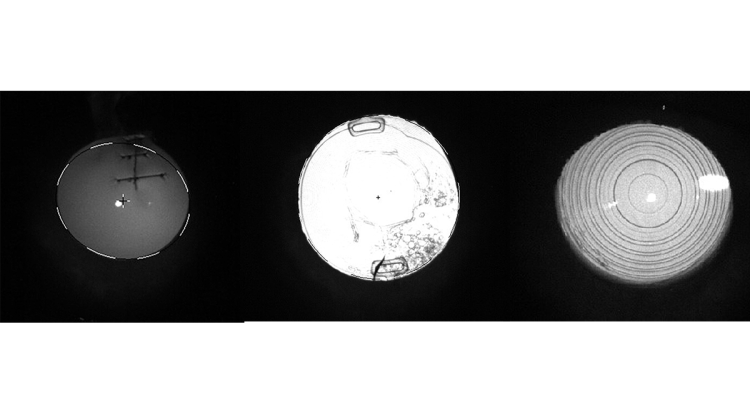

Die in Abbildung 1 gezeigten Auswertungen werden zusammen mit den Kunden besprochen. Bei der Bewertung der Messungen gehen wir in der Beratung schrittweise vor. In den Scheimpflugbildern kann die Transparenz der Hornhaut beurteilt werden, mögliche Hornhautnarben oder -trübungen leuchten im Schnittbild stärker auf. Die Augenlinse wird ebenfalls durchleuchtet und lässt einen Rückschluss auf den Transparenzgrad zu. Hier hilft auch die Retroillumination enorm (Abb. 2). Somit kann sich der Optometrist ein Bild über die Abbildungsfähigkeit des Auges machen. Unseren Kunden erklären wir die Aufnahmen – für viele ist dadurch ihr täglicher Seheindruck besser verständlich.

Abb. 2: (Links) Alle im Strahlengang befindlichen „Ablenkungen“ sind dank der Retroillumination gut erkennbar. Eine vertikale Hornhautperforation wurde mit Einzelknüpfnähten versorgt. An den Einstichstellen des Nahtmaterials sieht man die Zugkräfte des Fadens. (Mitte) Zu erkennen sind eine Intraokularlinse und die Ansatzbereiche der Haptiken. Die Kasulorhexis ist nur wenige Millimeter groß und im inferioren Bereich sind Elschnig-Perlen des Nachstars zu erkennen. (Rechts) Die konzentrischen Ringe einer Multifokal-Intraokularlinse heben sich deutlich im Retroilluminationsbild ab. Damit lassen sich Zentrierung und Lage der Intraokularlinse im Vergleich zum Pupillenzentrum beurteilen.